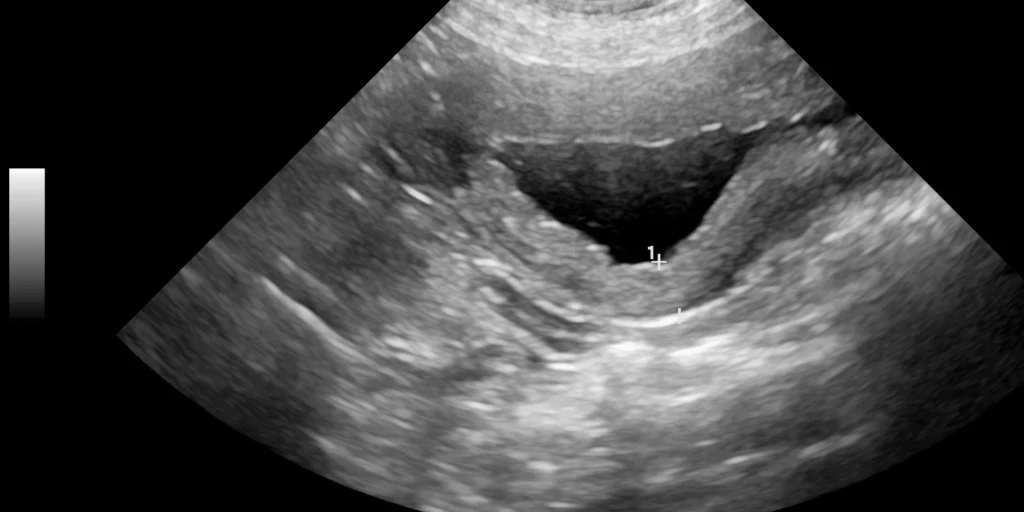

Tumore

Blasentumore verursachen keine Blasenentzündung, zeigen aber ähnliche Symptome wie Harnsteine oder Blasenentzündungen. Eine genaue Diagnose erfordert eine Ultraschalluntersuchung, da Tumore so gut sichtbar sind.

Blasentumore sind meist bösartig und treten vor allem bei Katzen über zehn Jahren auf. Da sie lange schmerzfrei bleiben, werden sie oft erst im fortgeschrittenen Stadium erkannt, was die Behandlung erschwert.